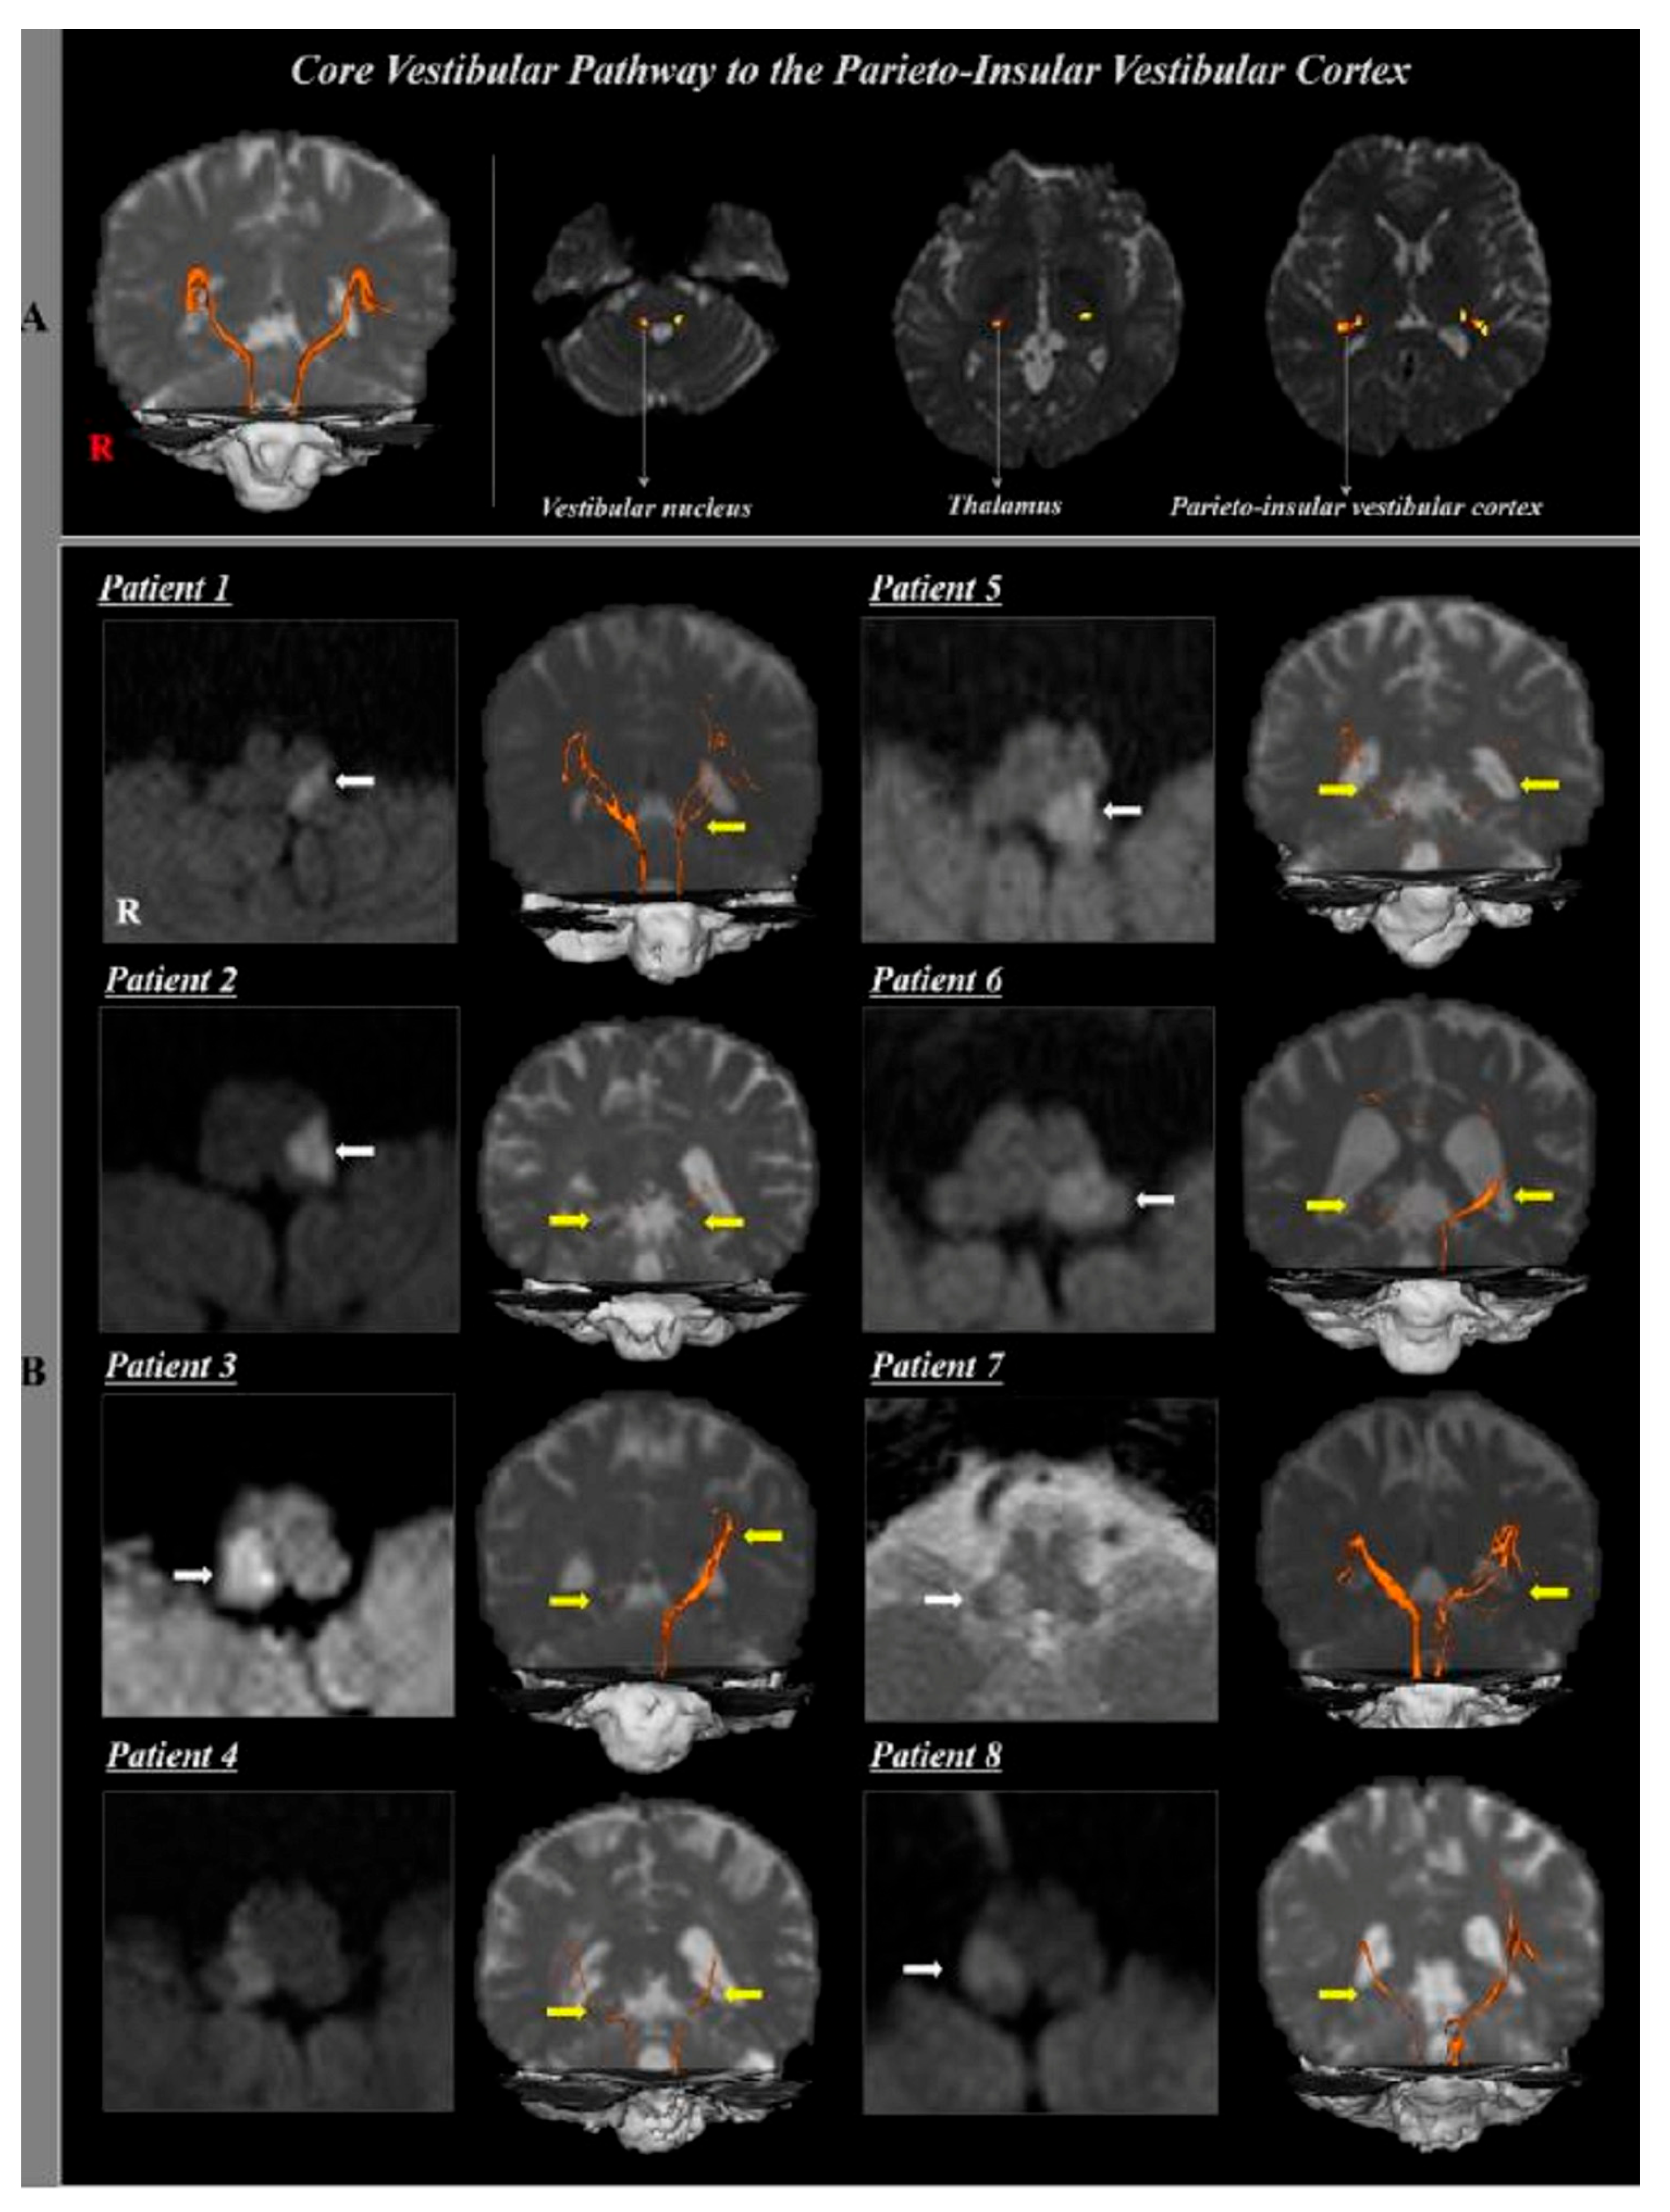

Yeo et al. (2018) used DTT in stroke patients (experimental group, n = 8, lateral medullary syndrome) and healthy individuals (control group, n = 10) to study the association between damage to the core vestibular pathway (connecting the parieto-insular vestibular cortex (PIVC) and vestibular nuclei) and symptoms of central vestibular disorder [39] (Figure 5). The experimental group demonstrated symptoms of central vestibular disorder (vertigo [n = 7], dysphagia [n = 6], ataxia [n = 5], dysarthria [n = 3]). The DTT results for the core vestibular pathway were compared between the two groups. The results presented no significant difference between the two groups in FA and MD of the core vestibular pathway, but both the affected side and non-affected side of the experimental group significantly decreased in tract volume compared to the control group. The results confirm that damage to the core vestibular pathway is highly associated with dysphagia. Some limitations of the research include (1) the small number of subjects, making it difficult to generalize the results; (2) the tract volume of the fiber tract of the core vestibular pathway, which may have been underestimated or overestimated; (3) the contralateral vestibular pathway on the non-affected side that could not be reconstructed; (4) the vestibular nuclei area for seed regions of interest, which was too small to define accurately; and (5) the lack of explanation of the degree of reconstruction of the left and right tracts and the difference between moderate and sub-severe symptoms of central vestibular disorder.

Figure 5.

Anatomical structure of CVP captured using DTT [39]. (A) Core vestibular pathway to the PIVC in normal control subject (53-year-old male) (B) Computed tomography (CT) and diffusion tensor tractography (DTT) of the core vestibular pathway to the PIVC in eight patients with dorsolateral medullary infarct (white arrow).; bilateral or unilateral core vestibular pathway to the PIVC were injured due to dorsolateral medullary infarct (yellow arrow). Copyright by Yeo et al. (2018) [39].